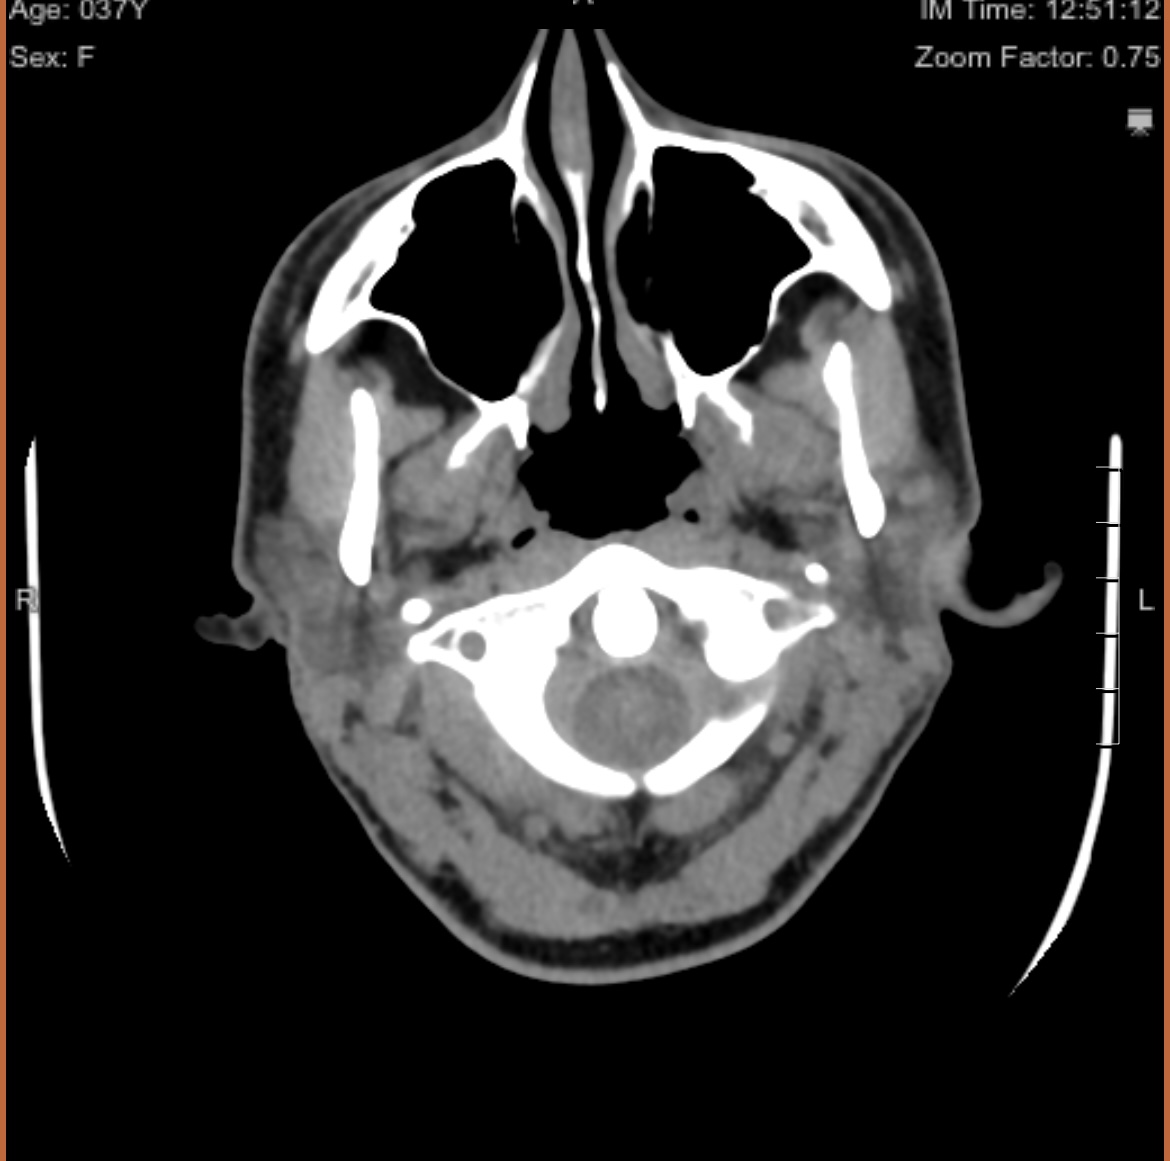

Hi- I think I may have found what you were asking for. Thanks again for your time, it’s beyond appreciated.

Hi @SeekingInfo yes they are the ones. Both your Styloids are extremely close to your C1 transverse process. I would assume therefore that you will have vascular compression probably IJV. Hopefully other members will give you their opinions shortly.

I think it would be really beneficial to get a CT with contrast, but I am fairly sure you will need the calcified ligaments removed anyway.

@SeekingInfo this is perfect, see attached annotated image.

Your styloids are extremely close to your C1, practically touching. This is important because the IJVs and vagus nerves (and also spinal accessory nerve) run between the styloids and IJV.

Research shows that the average space between a styloid and C1 in a healthy individual is about 9mm. I’d be surprised if you have more than 1.5mm between your styloids and C1.

I would recommend getting both styloids removed and to make 100% sure that whichever surgeon you decide to go with cuts the styloids above the level of C1. If they do not cut them above C1 you are going to continue to experience IJV compression symptoms.

I agree with @Rosie that a CT with contrast would be beneficial. However, most ES surgeons (the reputable ones) are going to look at the CT you already have and just know that those daggers need removed. And if they remove them above C1 then it’s all good. Some surgeons require the contrast CT though, so maybe they won’t even look at your CT without contrast, but it depends on the surgeon.